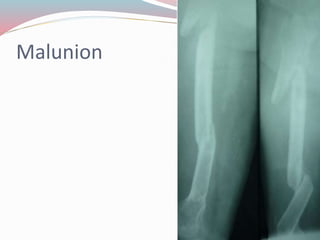

๏‚— Malunion

Malunion

COMPLICATION OF FRACTURE ๏‚—Delayed union ๏‚— Nonunion ๏‚— Malunion ๏‚— AVN ๏‚— Traumatic subperiosteal ossification ๏‚— Myositis osificans ๏‚— Sudeckโ€™s osteodystrophy